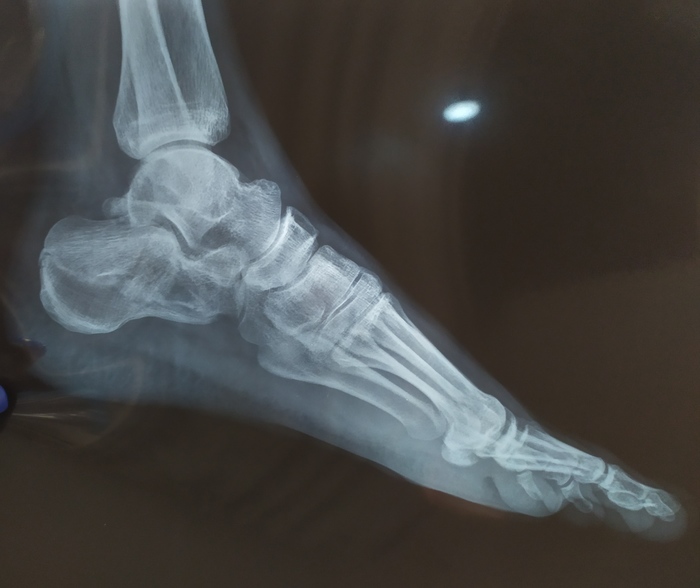

Примерочный вариант.